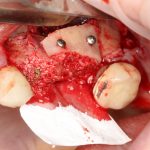

Устанавливаем формирователи десневой манжеты. Сегодня я называю эту процедуру не менее важной, чем любой другой этап имплантологического лечения:

И швы. Просто швы. Никаких дополнительных процедур.

Если честно, то сейчас бы я использовал другой шовный материал и другой тип швов. Одно неизменно, — и я об этом много раз говорил, — самая широкая часть формирователя десны должна находиться на уровне десны. Так, чтобы эффективно отрабатывать т. н. «биологическую ширину».

Через неделю я снял швы, а мой коллега Андрей Карнеев (дело было еще в НИЦ) приступил к изготовлению протезов. На это ушло полторы недели: